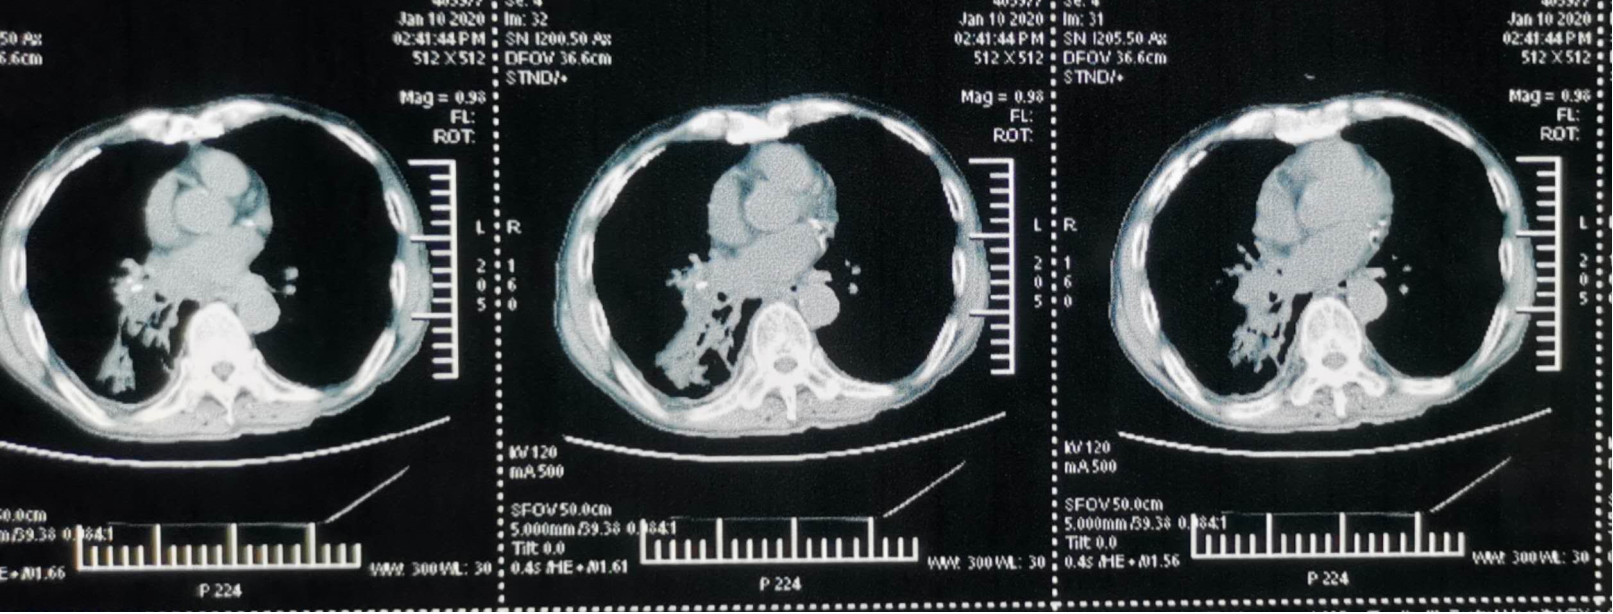

2020-01-10 胸部CT(图1):符合右肺癌伴肺门及纵隔淋巴结转移;考虑右肺下叶基底段阻塞性炎症改变及充气不良;考虑右肺下叶背段肺不张;右肺下叶癌性淋巴管炎不除外;考虑右中叶陈旧病变可能大;两侧肺气肿、多发肺气囊;右下叶基底段支气管痰栓;右侧胸膜病变,转移不除外;右侧胸腔积液;肝脏囊肿;考虑双侧肾上腺转移;腰1骨转移不除外。

2020-01-13 全腹CT(图2):两侧肾上腺多发结节影,考虑转移瘤;两侧肾上腺多发结节影,考虑转移瘤;左侧肾周软组织密度微小结节影,不除外转移;左侧髂骨翼髋关节前内侧较大团状混杂密度影,考虑转移;左侧髂骨翼、胸12椎体局部骨质吸收破坏,考虑转移;腹腔内、腹膜后、盆腔及两侧腹股沟多发小淋巴结。

2020-01-13头部CT(图3):未见明显异常。

在诊断方面,患者于外院行支气管镜活检病理提示腺鳞癌,但未系统治疗。后为求进一步诊治转入我院,经完善胸部CT、全腹CT、头颅CT等影像学检查,并结合穿刺活检、免疫组化及基因检测,最终明确诊断为原发性支气管ASC,伴右肺门、纵隔淋巴结转移,以及骨、肾上腺、胸膜、左下腹软组织等多发转移。